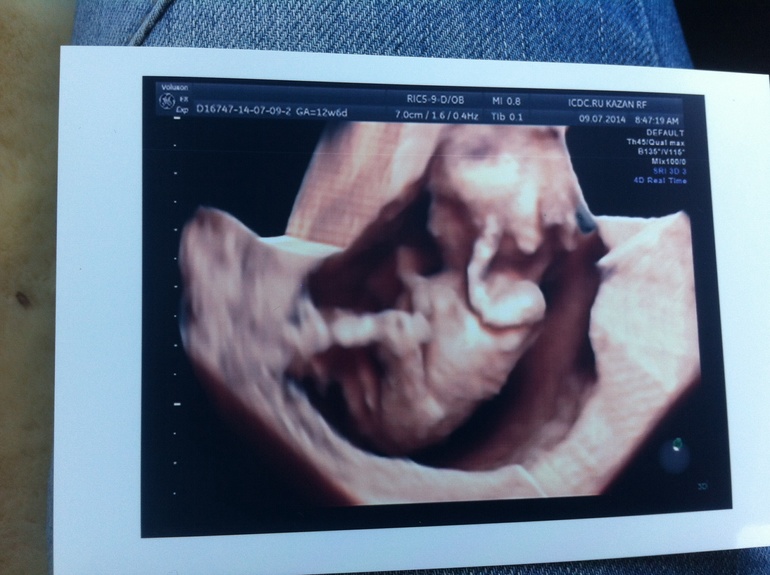

Ох бабоньки, только вышла с узи!!! все хорошо, все параметры соответствуют сроку, шейка отличная, и вообще все прекрасно!!! а еще у нас будет девочка!!!!! я так рада!!! вот и пошли все кто говорил что не надо так сильно хотеть именно девочку!!! надо!!! мы хотели: нате получите!!! вообще я так рада всему и главное что дитё живо здорово растет и развиваеться))))